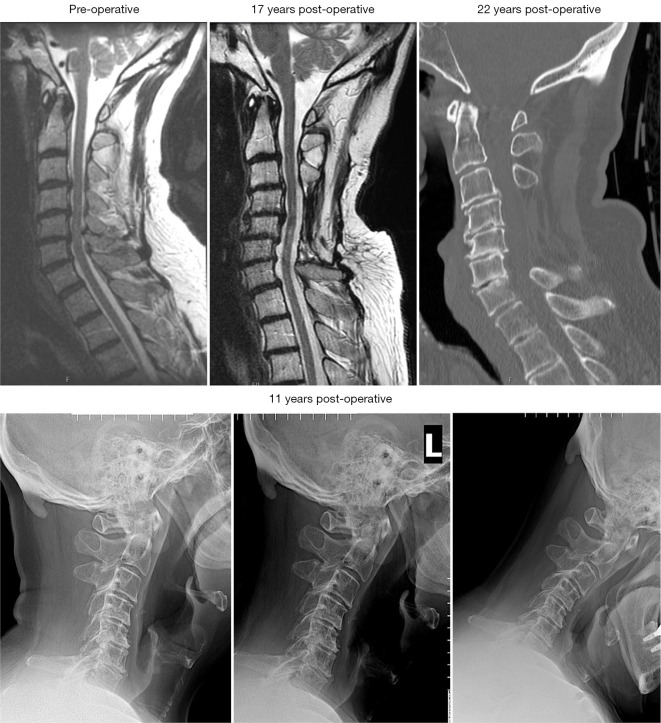

Background: Cervical laminectomy may be underutilized in the treatment of cervical spondylotic myelopathy (CSM) due to concerns regarding potential for post-operative instability and/or kyphosis. The purpose of this retrospective, observational study is to assess the short-term clinical and radiological outcomes as well as complications associated with a group of carefully selected patients who underwent laminectomy alone for CSM and compared them to a cohort of patients who underwent laminectomy with fusion.

Results: Forty-one patients who underwent laminectomy alone and 13 patients who underwent laminectomy with fusion were identified who met inclusion criteria. Both groups demonstrated significant improvement on Nurick and JOA scores postoperatively. Two patients in the laminectomy alone group required a subsequent one-level anterior cervical discectomy and fusion for onset of postoperative neck pain, without neurological symptoms or new deficits in the follow up period. There was no difference in rates of post-operative kyphosis between the groups.

Conclusions: In appropriately selected patients without pre-operative kyphosis or abnormal motion on flexion-extension films, cervical laminectomy remains a safe and effective treatment option.